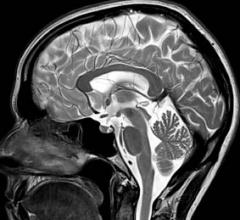

MRI creates images from the magnetic resonance created in hydrogen atoms when they are polarized and an electromagnetic pulse is used to knock them off axis. This section includes MR analysis software, MRI scanners, gadolinium contrast agents and related magnetic resonance imaging accessories.